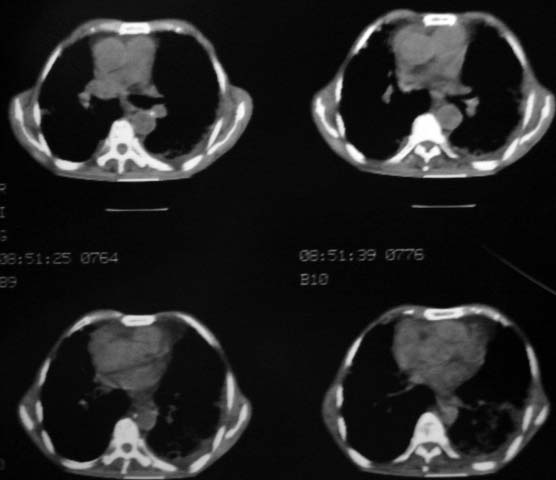

男,85岁,发热2月, 血常规:hgb99g/l.rbc2.55×1012/l.wbc3.8×109/l.n78.2%  l20.7% m1.1%.  hct26.3% .血沉20mm/hg.痰检结核杆菌阴性。ddp阳性。痰少粘稠色白。无咳血。

1.右上肺陈旧性肺结核灶;

右上肺陈旧性肺结核灶,双肺感染灶〔大部份纤维化〕,肺气肿.

双肺继发型肺结核,肺纤维化,肺气肿,胸膜肥厚黏连。